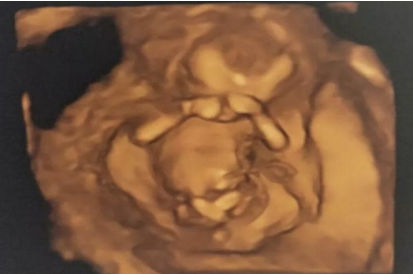

NT是胎兒頸后透明層厚度 (nuchal translusancy thickness) 的首字母縮寫,是一項(xiàng)臨床用于早期篩查胎兒異常的超聲軟指標(biāo)。通常在妊娠11~13+6周通過(guò)超聲測(cè)量。

人體的血液循環(huán)系統(tǒng)和淋巴循環(huán)系統(tǒng)的發(fā)育是不同步的,孕14周之前,胎兒的淋巴系統(tǒng)發(fā)育尚不完善,會(huì)有少量的淋巴液聚集在胎兒頸部淋巴管內(nèi),從而形成NT。孕14周后,胎兒淋巴系統(tǒng)發(fā)育逐漸完善,聚集的淋巴液迅速流入頸內(nèi)靜脈,NT就消失了,故做NT的時(shí)間要求在妊娠11~13+6周。

測(cè)量NT的最佳時(shí)間為孕11周~孕13+6周之間。查的太早NT還沒(méi)形成,孕14周之后,NT會(huì)消失。